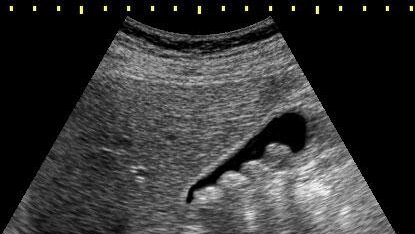

Все привыкли, что при камнях в желчном может помочь только хирургическое удаление желчного пузыря вместе с камнями – холицестэктомия. Почему 99% врачей выбирают этот путь? Потому что желчнокаменная болезнь не исчезает сама по себе. Если ничего не менять и кардинально не изменить привычки, питание и образ жизни, камни будут формироваться снова и снова. Делать повторную операцию, которая как и любое хирургическое вмешательство, имеет свои риски и нюансы, никто не хочет. Поэтому у врачей «лечение» одно – удаление желчного пузыря...

Почему желчный пузырь нельзя удалять. Мифы об операции по удалению желчного. С камнями в желчном можно жить спокойно.